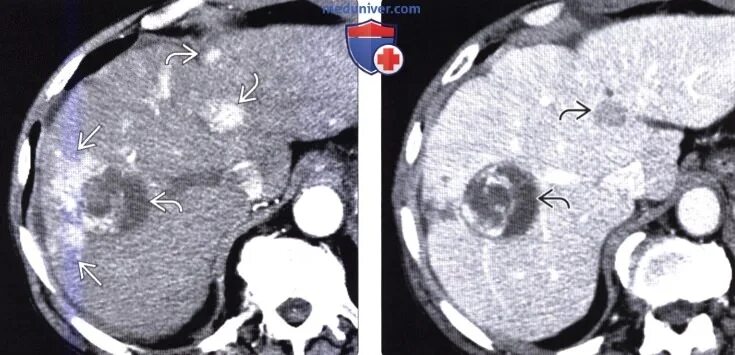

Плотность печени на кт